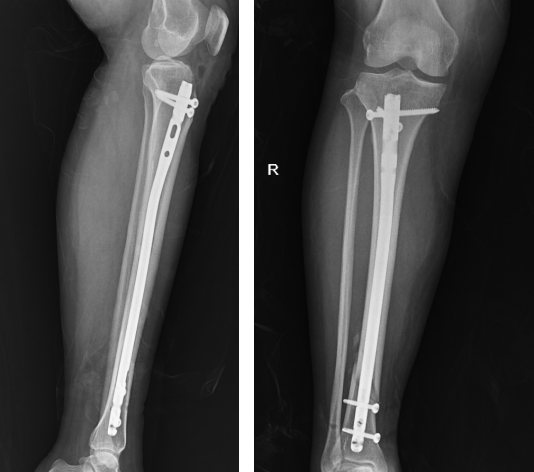

手术过程顺利,术后的影像学检查显示,骨折部位得到了精准复位和固定。与传统的骨折切开复位钢板内固定手术相比,此次采用的髓内钉内固定术具有切口小、创伤少、固定效果好等显著优势,极大地缩短了骨折愈合时间和患者行动能力的恢复周期,有效减轻了患者的痛苦。

术后复查